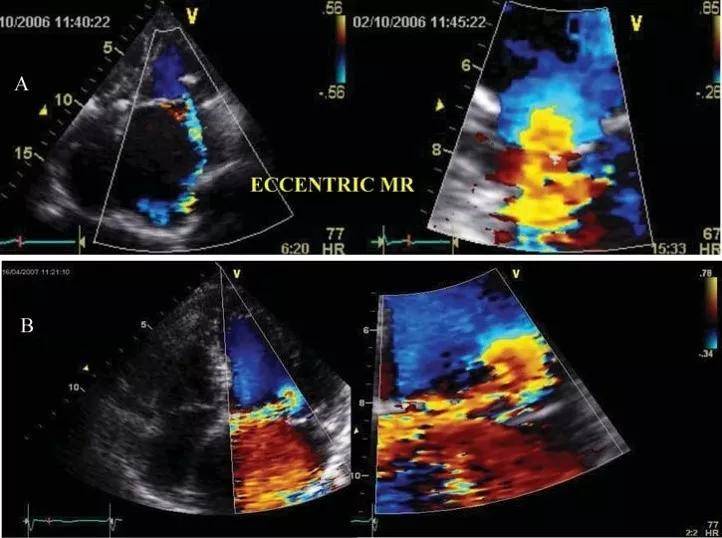

超声心动图十大基本功8.2:二尖瓣关闭不全的超声评估